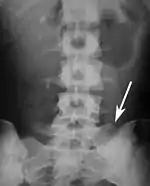

Lumbarization of sacral vertebra 1, seen as 6 vertebrae that do not connect to ribs.

Sacralization of the L5 vertebra is seen at the lower right of the image.